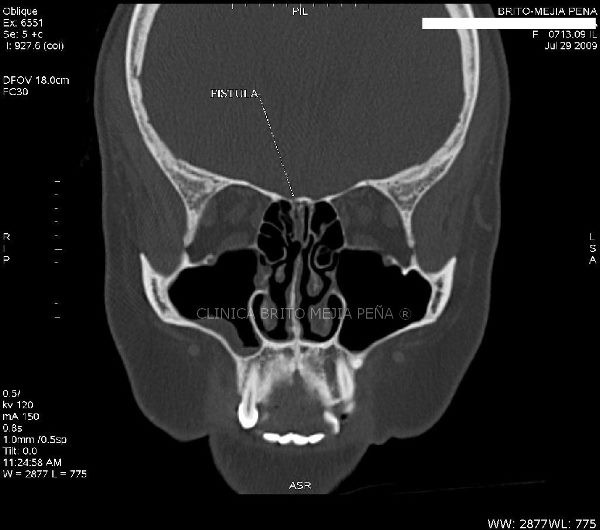

Fístula LCR axilar

Fístula LCR sagital

Fístula LCR coronal